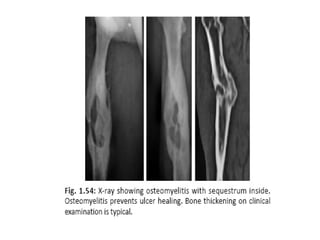

• X-ray of the part to look for

periostitis/osteomyelitis.

• X-ray ofthe part to look for periostitis/osteomyelitis. • FNAC of the lymph node. • Chest X-ray, • Haemoglobin, ESR, total WBC count, serum protein estimation (albumin).